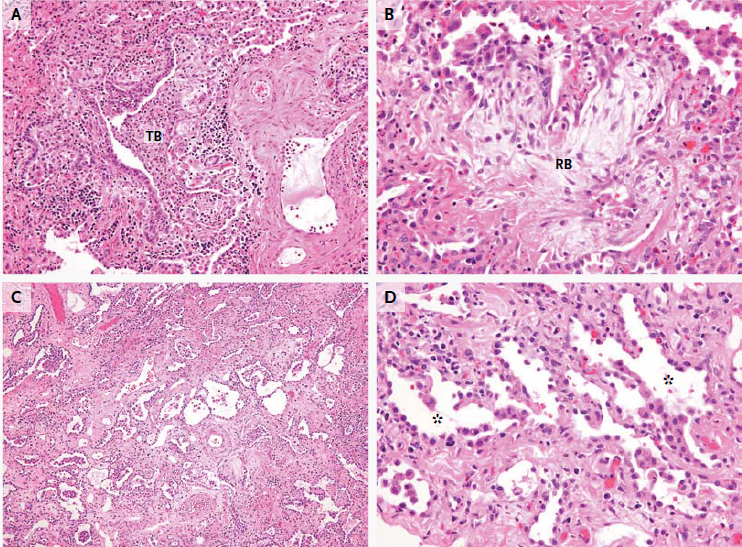

El examen de las muestras de biopsia de la etmoidal posterior izquierda y senos esfenoidales mostraron mucosa nasosinusal con un tejido linfoide denso subyacente en un fondo de la fibrosis. Las células linfoides eran grandes, y la tinción inmunohistoquímica para CD20, un antígeno de células B, fue positivo, lo que confirma el diagnóstico de linfoma difuso de células B grandes (Figura 3A, 3B y 3C).

Figura 3

Biopsia muestras de la Izquierda Posterior etmoides y esfenoides senos

En la tinción con hematoxilina y eosina, las muestras de biopsia del etmoides posterior izquierda y senos esfenoidales revelaron mucosa nasosinusal con un tejido linfoide subyacente infiltrante en un fondo de fibrosis moderada (Panel A). Las células linfoides eran grandes, con núcleos irregulares multilobulados, cromatina vesicular y nucleolos prominentes ocasionales (Grupo B). La tinción inmunohistoquímica para CD20 fue difusamente positiva (Grupo C), lo que confirma el diagnóstico de linfoma difuso de células B. En la tinción inmunohistoquímica adicional, las células tumorales fueron difusamente positiva para CD10 (Panel D) y CD30 (Panel E), y la mayoría de las células tumorales eran de forma variable positiva para el linfoma de células B 2 proteínas (BCL2) (Panel F).

El linfoma difuso de células B representa un grupo de cánceres biológicamente heterogéneos que se pueden dividir morfológica, genética e inmunofenotípicamente y que incluyen ciertas entidades específicas.14 La mayoría de los casos no cumplen los criterios diagnósticos de una de las entidades patológicas específicas y son clasificados como linfoma difuso de células B. Un examen más detallado inmunofenotípico del tumor de esta paciente reveló que las grandes células B fueron positivas para antígenos del centro germinal CD10 y linfoma de células B 6 proteínas (BCL6) y fueron negativos para el post-germinal centro mieloma múltiple marcador oncogén 1 (MUM1, también conocido como factor regulador de interferón 4), los hallazgos que indican que el linfoma es de origen germinal-centro, en lugar de origen nongerminal-centro (Figura 3D) 0,15 mayoría de las células tumorales fueron positivas para la proteína antiapoptótica marcador linfoma de células B (2 BCL2) (Figura 3F), 50% de las células tumorales fueron positivas para el antígeno de proliferación Ki-67, y 10% de las células tumorales fueron positivas para MYC. La ausencia de una alta expresión concurrente de BCL2 y MYC indica que este tumor está en un subgrupo de linfoma difuso de células B que se asocia con un mejor pronóstico, en comparación con el subgrupo de tumores que muestran alta expresión concurrente de MYC y BCL2.16 , 17 Las células tumorales fueron también fuertemente y de forma difusa positivas para CD30, un antígeno de activación (Figura 3E); un ARN en el ensayo de hibridación in situ fue negativo para el virus de Epstein-Barr.